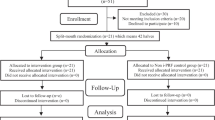

In each subject, the allocation of control and experimental sides (right vs. left) was done using a computer random number generator software (Microsoft Excel, Microsoft, Washington, USA). The patient allocation and their follow-up process during the study period are mentioned in Fig. 1. The outcome assessor was blinded during study model and biochemical assessment stages.

Thirty-six extraction sockets in 18 subjects were randomly allocated to experimental and control sides of 18 each. Two subjects were lost to follow-up due to COVID-19 lockdown, and the remaining 16 subjects were followed till the end of study period. The CONSORT flow diagram is shown in Fig. 1.